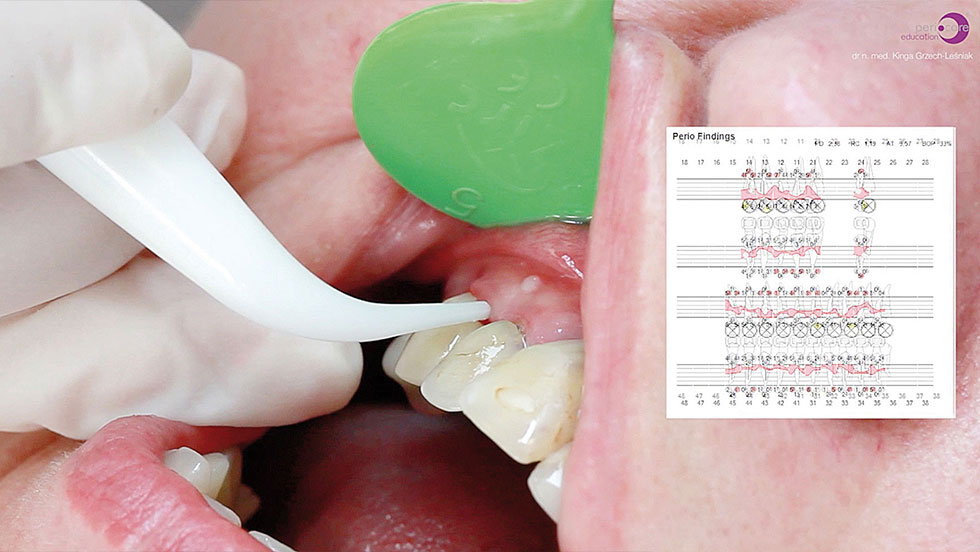

Η λεπτομερής κλινική εξέταση θα περιελάμβανε, μεταξύ των άλλων, στοιχεία σχετικά με το βάθος των περιοδοντικών θυλάκων (ΒΘ), την αιμορραγία κατά την ανίχνευση (ΑΚΑ) και τον δείκτη πλάκας (ΔΠ).

Πριν τη θεραπεία, η ασθενής υποβλήθηκε σε διαδικασία υποουλικού καθαρισμού με ξέστρα υπερήχων. Μετά τον καθαρισμό, η κλινική κατάσταση της ασθενούς βελτιώθηκε. Στη συνέχεια, εφαρμόστηκε ένα laser Nd:YAG για την αποστείρωση και την απολύμανση των περιοδοντικών θυλάκων (Εικ. 3 έως 7) και laser Er:YAG για την απομάκρυνση της υποουλικής τρυγίας (Εικ. 8 έως 12).

Για την τελική απολύμανση και αποστείρωση του πήγματος ινικής, εφαρμόστηκε και πάλι το laser Nd:YAG (Εικ. 13 και 14). Στην Εικ. 15 φαίνεται η κατάσταση αμέσως μετά τη χειρουργική με laser Er:YAG και την απολύμανση των περιοδοντικών θυλάκων με Nd:YAG